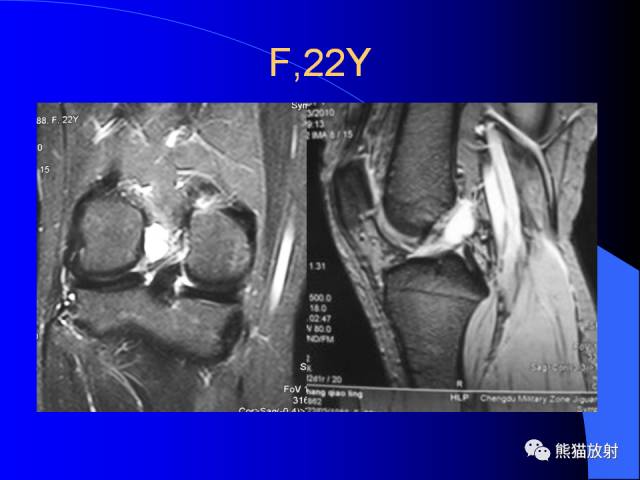

膝关节周围囊肿MRI

膝关节周围囊肿是较常见的病变,可以是原发的,多见于青年及儿童,囊内容物通常是黏液;也可以是继发的,多与关节腔相通,内含一般黏性的滑液,常继发于膝关节骨关节炎、类风湿关节炎、非特异性滑膜炎、半月板损伤、髌骨软骨软化症等。

腘窝囊肿是膝关节周围最常见的囊肿。